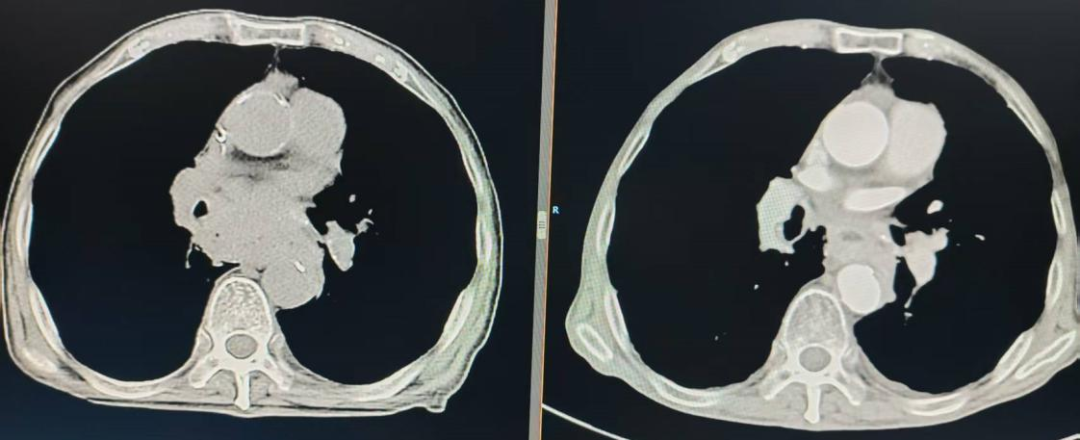

经过2个月的精准放疗,奇迹出现了。丁某的肿瘤体积缩小超过70%,吞咽困难症状明显缓解。在放疗科团队的精心操作下,丁某顺利完成全程调强放射治疗,治疗过程中耐受性良好,未出现严重不良反应。